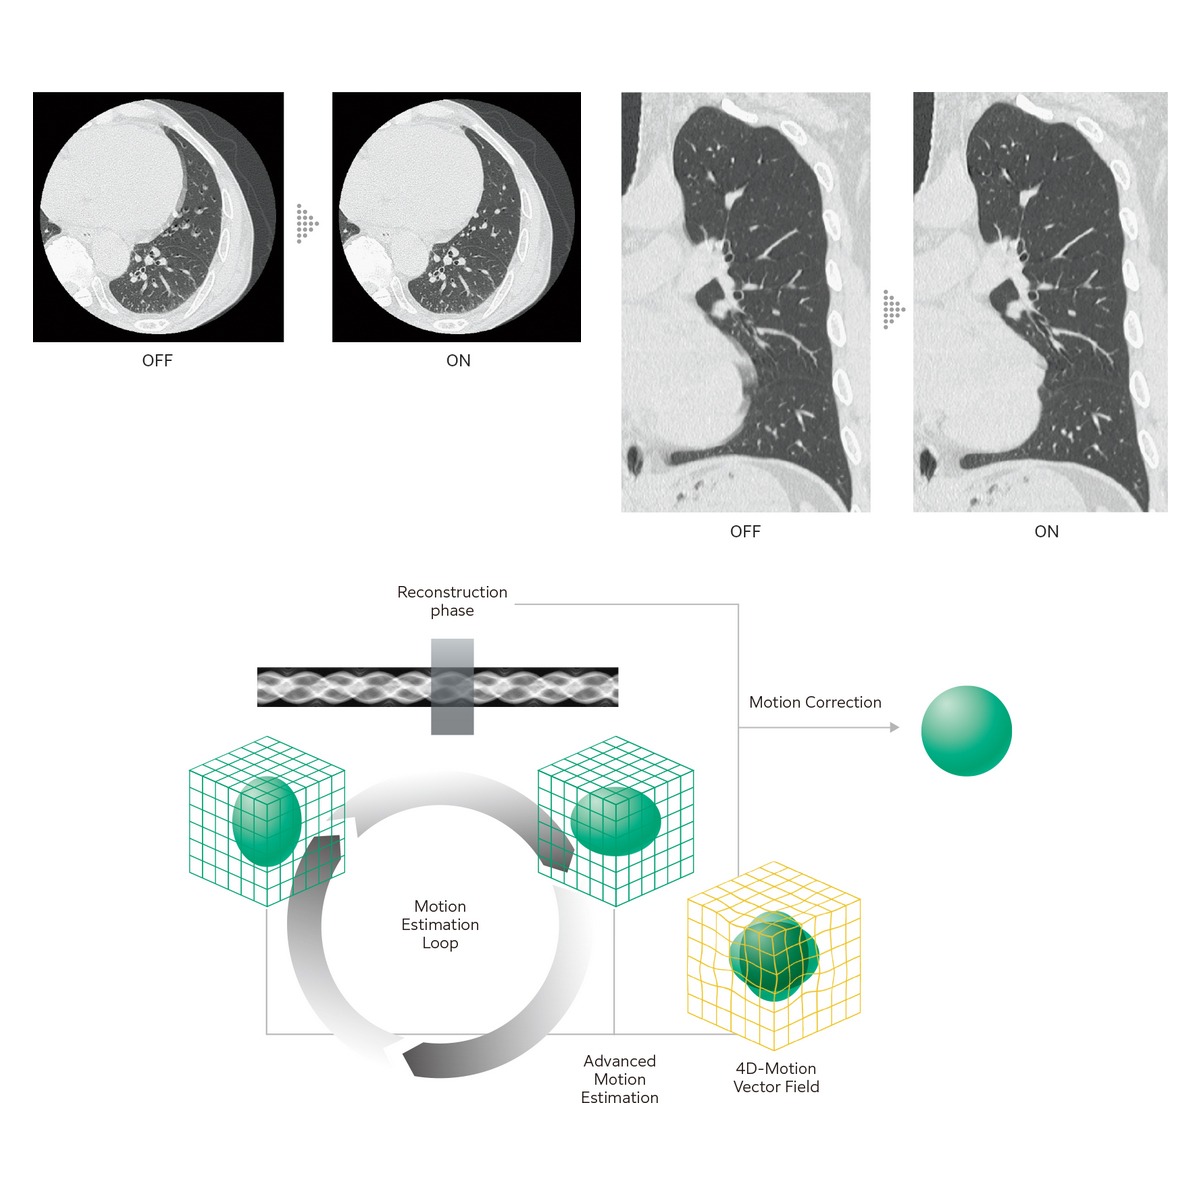

Body StillShot "抑える技術"を胸部領域全体に拡大心臓CT検査(心電同期撮影)において適用可能であった動き抑制技術を、さらなる臨床現場での要望を叶えるべくCT検査(非同期撮影)に拡張しました。Body StillShotは、収集したRawDataから被写体の動く方向と量を4次元的に算出する際に、体軸方向の連続性を広範囲に維持することで動きによるブレの少ない画像を提供します。心電情報を必要としない演算アルゴリズムを採用することで、ルーチン検査への適用が容易になります。AI技術を活用して開発した画像再構成技術IPV*2との併用も可能で、さらなる高画質化に寄与します。